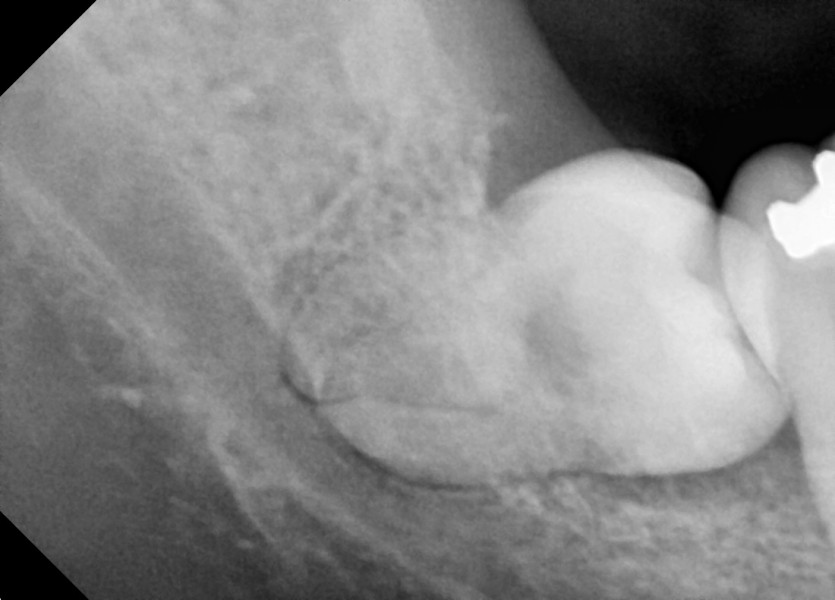

#38,48 사랑니 발치

구강 외과 전문의가 당일 발치했습니다.